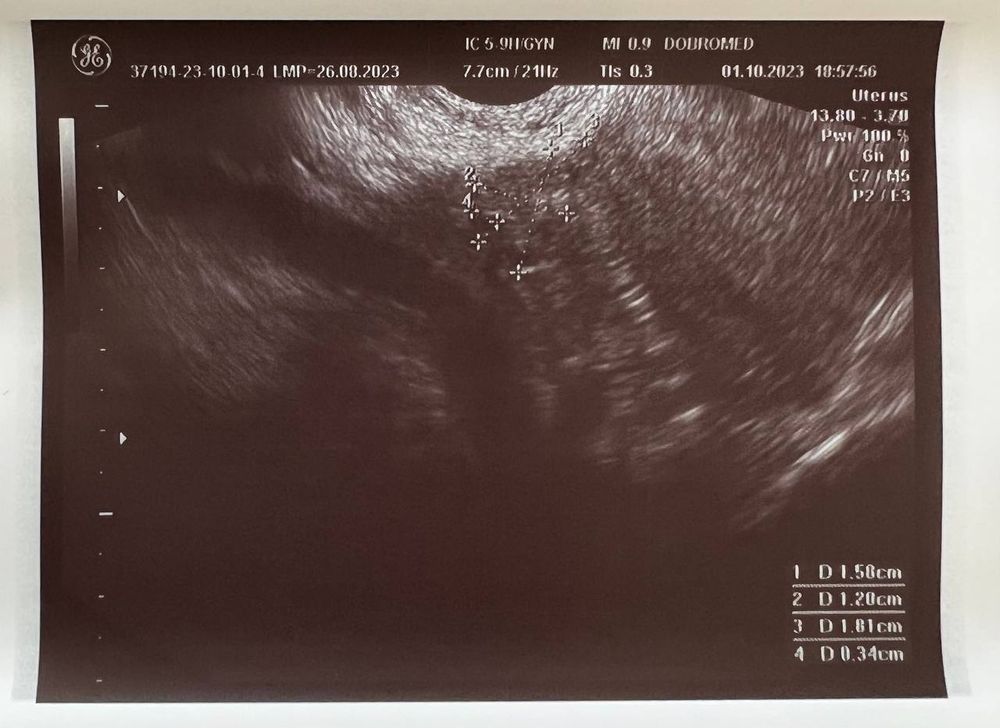

Вчера (1 октября) сходила на УЗИ, беременность подтвердили, маточная.

Размер плодного яйца 4 мм.

Но не видно желтое тело, и мутное содержимое плодного яйца (как она сказала). Меня напугала очень узистка... мол, может быть замершая беременность.

Если есть специалисты тут - пожалуйста, посмотрите снимок